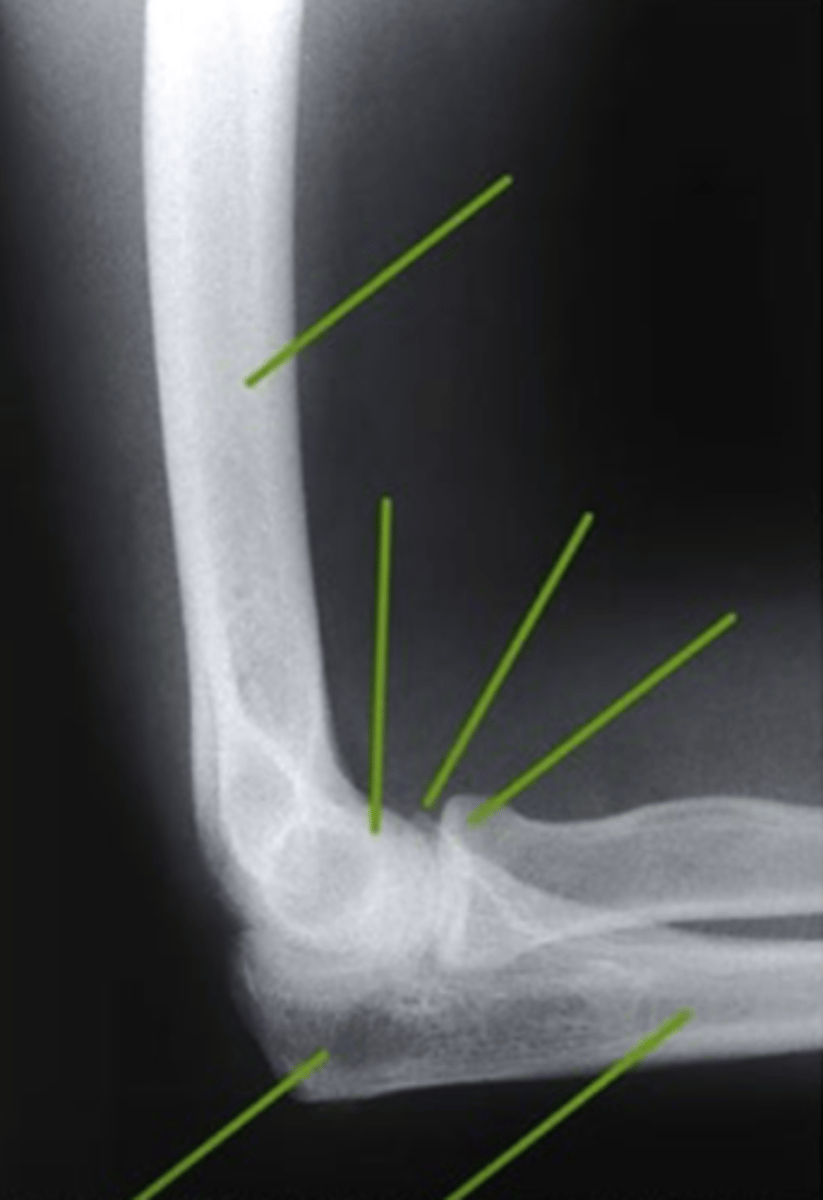

AP Elbow

what view is this

lateral epicondyle

what does the pink line point to?

medial epicondyle

Capitulum

coronoid process

shaft of ulna

shaft of the radius

radial tuberosity

radial head

radial neck